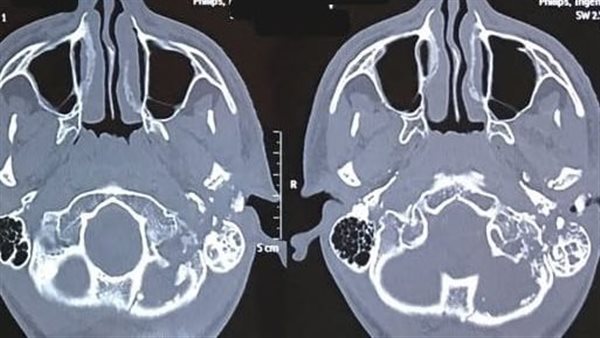

رصاصة خلف أذنه اليسرى وقطع تام بالعصب الوجهي السابع

وكان المستشفى الرئيسي استقبل شاب يبلغ من العمر 16 عاما، في حالة غيبوبة، نتيجة استقرار رصاصة خلف أذنه اليسرى، مما تسبب في قطع تام بالعصب الوجهي السابع، وبعد قضاء أسبوعين في العناية المركزة، خضع المريض لعملية جراحية دقيقة لاستكشاف العصب السابع، ثم حدد الدكتور محمد محمود رشدي، مكان القطع في العصب، ونظرًا لتلف جزء كبير من العصب، أجرى الدكتور محمد مدثر أبو شنيف، عملية جراحية استغرقت 6 ساعات، لأخذ وصلة عصبية من أحد الأعصاب الحسية الجلدية وإعادة توصيل العصب السابع بالعصب المسئول عن حركة اللسان، دون أي تأثير على حركة اللسان ولتستقر حالة المريض، إذ أظهرت المتابعة المستمرة تحسنا ملحوظا في عضلات الوجه، وعادت حركة الوجه إلى طبيعتها بشكل كامل، ليعود الشاب لممارسة حياته بشكل طبيعي بعد أكثر من عام من المتابعة الدقيقة.